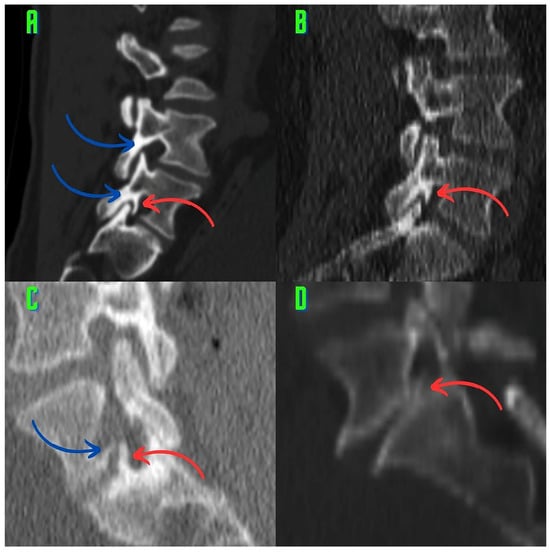

2.3. Image Analysis and Research Methods